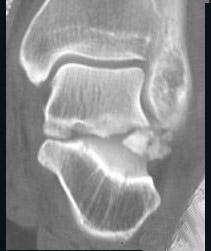

问题 男,28岁,从高处坠落后双足剧痛一月余,请结合影像学检查,选出最可能的诊断 ( )

选项 A、舟状骨骨折 B、楔骨骨折 C、骰骨骨折 D、距骨骨折 E、跟骨骨折

答案 D